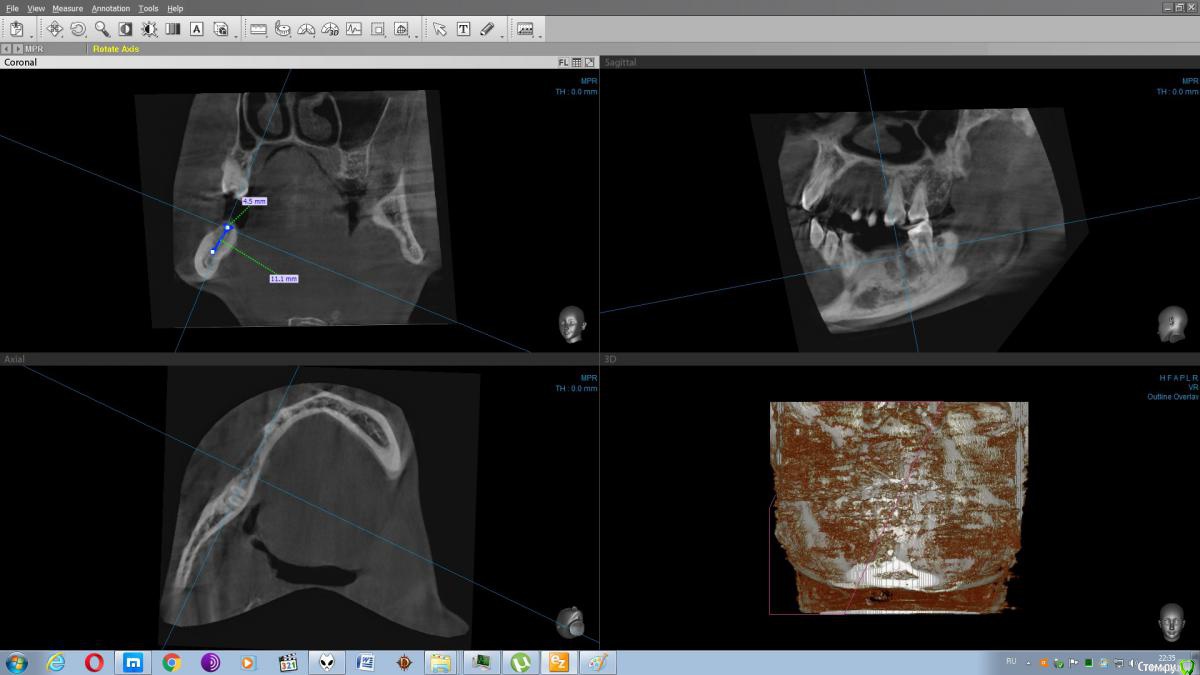

Галич Опубликовано 11 июня, 2020 Автор Поделиться Опубликовано 11 июня, 2020 Есть КТ Ссылка на комментарий

Irouil Опубликовано 15 июня, 2020 Поделиться Опубликовано 15 июня, 2020 Создаётся впечатление, что можно установить два имплантата без проведения костной пластики Ссылка на комментарий

колесников Опубликовано 16 июня, 2020 Поделиться Опубликовано 16 июня, 2020 (изменено) Здравствуйте! Если нет возможности поставить 2 импланта,поставьте пока 5ку. 6ку одну Вы конечно можете поставить и сделать консоль на 5ку,но эта экономия может обернуться уменьшением срока службы импланта. Можно обойтись без костной пластики,выбрав соотвествующий имплант,но без десневой пластики не обойтись Изменено 16 июня, 2020 пользователем колесников Ссылка на комментарий